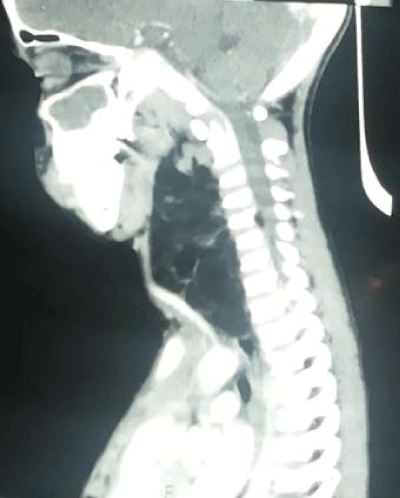

Contrast enhanced computed tomogram showed 10.2cmx5.5cmx5.2cm, large, uncapsulated diffusely infilterative lipomatous mass showing multiple thin and thick septations with nodularity. Superomedially the mass was extending into the parapharyngeal space and deviating the left oropharynx airway towards right. Posterosuperiorly the mass was extending in the prevertebral region with extension into the cervical neural foramina and foramen transversarium at C4-5; C5-6;C6-7 levels, causing widening of neural foramina with thinning and scalloping of adjacent pedicles and lamina (Figure 3). Anterosuperiorly the mass is displacing the carotid sheath anteriorly and medially the esophagus, larynx, trachea and thyroid gland were displaced contralaterally with no luminal narrowing. Inferiorly, small extension was seen into the superior mediastinum with splaying at the origin of left common carotid artery and left subclavian artery (Figure 4).

Figure 3:

Figure 4: